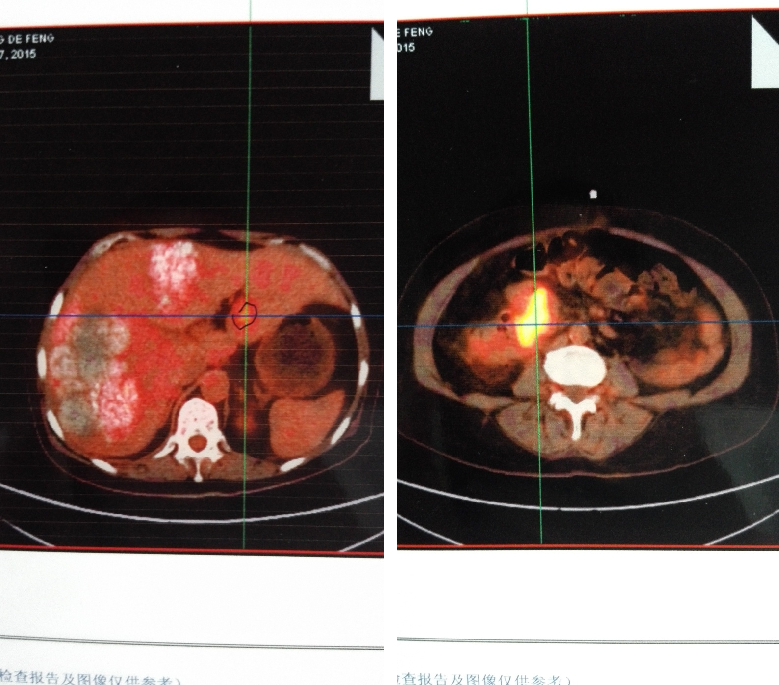

患者左肝为转移病灶,但右肝病灶性质无法明确,进一步行PET-CT检查:

①结肠肝曲肠壁明显增厚,FDG代谢增高,转移可能大;肠周数枚小结节,FDG代谢目前未见明显增高;肝左叶外侧段局灶性FDG代谢增高,MT不除外。

②肝脏明显增大,两叶广泛颗粒样钙化伴局部囊性密度影,考虑肝棘球蚴病可能。

实际治疗情况:患者行基因检测,KRAS、NRAS野生型,行西妥昔单抗+FOLFIRI方案化疗。

△治疗前